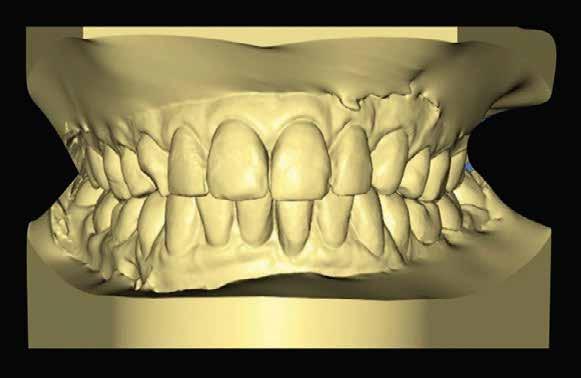

hatékonyan továbbítsuk a fogtechnikai laboratóriumba. Fontos azonban megjegyezni, hogy jelenleg nem áll rendelkezésre elegendő szakirodalmi adat, amely megerősíti, hogy az orális szkennerek segítségével lehetséges a rendkívül pontos és részletgazdag lenyomatok készítése. A CAD szoftver elengedhetetlen része a digitális fogászatnak. Ezeknek a programoknak a segítségével alakítjuk ki a virtuális térben azokat a restaurátumokat, amelyeket később teljesen automatizált gépek készítenek el a valóságban.

Szájterpesz használata mellett digitálisan intraorális fotók készültek a páciensről mind frontális, mind laterális és okkluzális irányokból. További fotók is készültek a páciensről egy digitális tükörreflexes kamera segítségével (frontális és laterális irányból, valamint 45 o-os szögből). Mindkét állcsontról digitális lenyomat készült egy intraorális szkenner segítségével (Care stream 3500). A maximális-interkuszpidációs helyzetet (IKP) szintén a Carestream 3500-as készülék felhasználásával rögzítet -

tük. Az új harapási magasságot a CAD/CAM szoftverben létrehozott virtuális artikulátor általunk meghatározott mértékig történő nyitásával határoztuk meg.

A páciens a megkezdett kezelések folytatása miatt 2017ben ismét felkereste a rendelőnket (7. ábra). Ekkor egy új intraorális lenyomatvétel történt (Carestream 3600).

A már előzetesen preparált felső frontfogak csiszolt csonkjainak megtartottuk az eredeti formáját. Az alsó és felső őrlőfogak preparációja nem volt szükséges (1.7-1.4, 2.4-2.7, 3.7-3.4, 4.4-4.7), az alsó kismetsző fogakat minimál invazív módon készítettük elő. Az előkészítést követően új digitális lenyomat készült. Az így kapott digitális adatokat továbbítottuk a fogtechnikai laboratóriumba (9. ábra). A virtuális modellt ezek alapján hozták létre (AnatomicLab), és a minta elkészítéséhez szükséges STL fájlt továbbították egy háromdimenziós nyomtatóra (SolFlex 650, VOCO), amely segítségével elkészítették az új mintát (V-Print model, VOCO).

A végső restaurátumokat (héjakat és koronákat) Ce-

ramill Mind tervező program segítségével (AmannGirrbach) digitálisan megtervezték, majd frézgép segítségével (CeramillMotion 2, AmannGirrbach) li thium-diszilikát tömbökből (VITABLOCS TriLuxe forte for CeramillMotion 2, AmannGirrbach) kifaragták (10. ábra). Miután a fogpróba során ellenőrizték és megfelelőnek találták a pótlások széli záródásának a pontosságát, valamint az elkészült restaurátumok esztétikai megjelenését, ezután egy ajak- és szájterpesz került felhelyezésre (OptraGate, IvoclarVivadent).